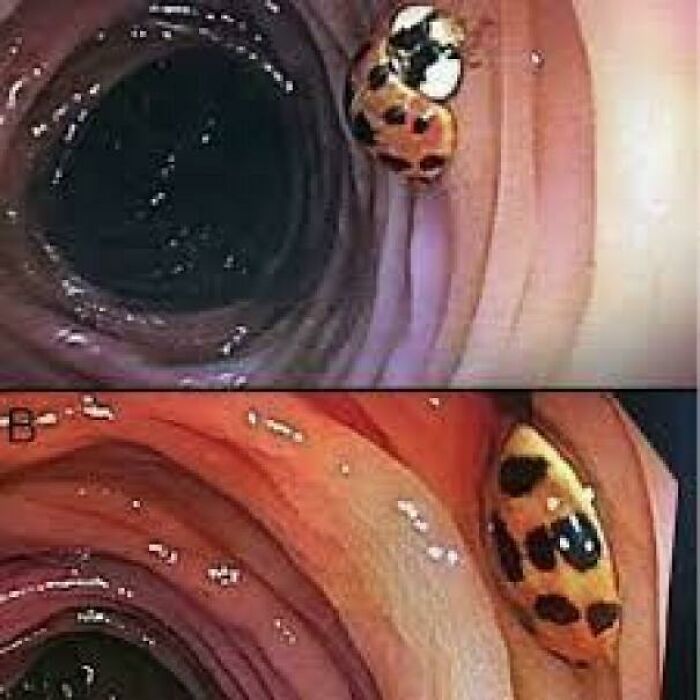

During A Colonoscopy Performed On A 59-Year-Old Man, An Unexpected Guest Was Found In His Intestine